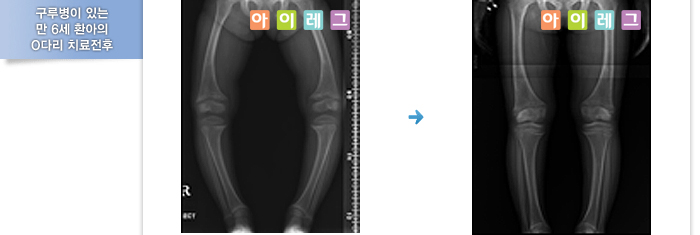

반면에 아이가 2세 이상이고 O다리가 심한 경우는 구루병(비타민D 결핍증)같은 대사성 질환과 연관되어 있을수 있기 때문에

정밀검사가 필요할 수 있고 경우에 따라 치료가 필요합니다. 아이가 성장하여 7세가 되었을 때 기형의 정도가 심각할 것으로 예상이 되면 나이에 관계없이 즉시 교정하여 주는 것이 바람직합니다.